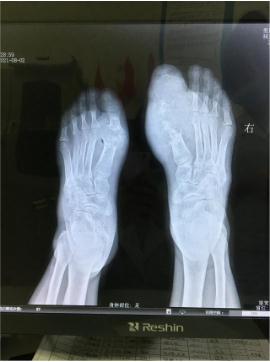

DR影像显示双足跖趾关节骨质严重被破坏

跖趾关节术后照

通过痛风石切除术、中医微创可视针刀镜关节清理术以及水筋针手术清理后,辅助一系列中医特色理疗,患者坐着轮椅来院,现在不仅双足大脚趾得以保全,行动与正常人差别并不大,活动范围改善了很多。小伙子为表示对朱院长的感谢,现场还向朱院长赠送了锦旗。